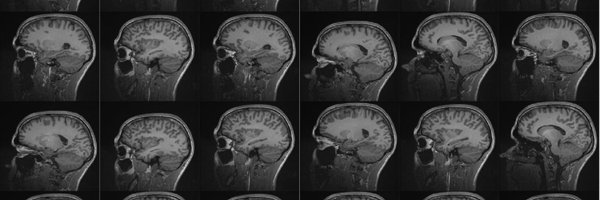

HOWEVER, we still saw some modest improvements in unfolded feature registration in MRI (sharper averages):